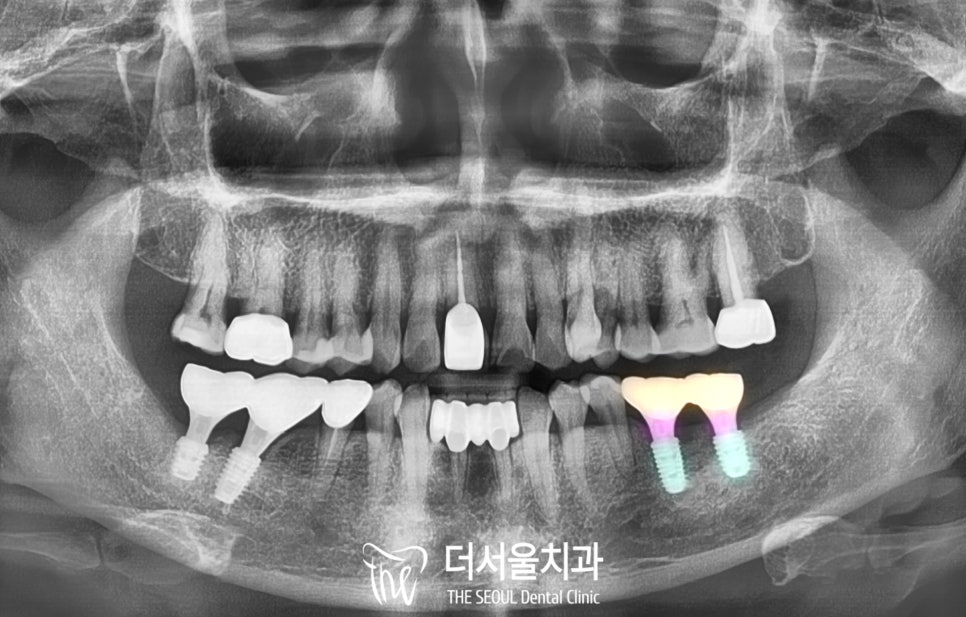

태평역치과 에서는

픽스처와 치조골이 잘 유착된 것을 확인한 뒤

그 위로 보철을 올려드리는데요,

커스텀 어버트먼트(custom abutment)라

부르는 맞춤형 연결 지대주를 활용합니다.

개인마다 치열이나 치아 크기도 다르고,

치조골의 상태에 따라

픽스처를 심은 깊이, 각도도 다르기에

이러한 작은 차이까지 고려하여

제작하는 개인 맞춤형 연결나사라고

생각하시면 됩니다.

커스텀 어버트먼트를 사용하여

최종 크라운까지 올려드린 사진을 보면

보이는 것처럼 두 개의 크라운은

연결하여 브릿지로 만들어 드렸습니다.

그렇게 하면 구치부의 힘을

더 잘 버틸 수 있습니다.

디지털 임플란트 후

보철을 제작할 때 교합면에 홀이 있는

SCRP tpye으로 제작합니다.

그래야 이후에도 저 공간을 통해

보철을 세척하거나

나사를 조여드리는 것과 같은

유지 보수를 할 수 있기 때문이죠.